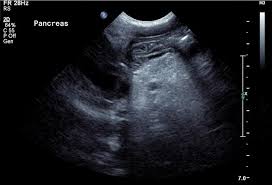

Schwartzman Diamond Syndrome : Figure 3 From Shwachman Diamond Syndrome Clinical Genetic And Radiological Study Semantic Scholar - Sds is the second most common inherited cause of pancreatic insufficiency.

Schwartzman Diamond Syndrome : Figure 3 From Shwachman Diamond Syndrome Clinical Genetic And Radiological Study Semantic Scholar - Sds is the second most common inherited cause of pancreatic insufficiency.. Phenotypic manifestations of sibling sets and isolated cases in a large patient cohort. Symptoms include the inability to digest food due to missing digestive. Shwachman diamond syndrome is considered as a rare ailment but gained medical attention as it the syndrome name is derived from its inventors, shwachman, diamond, et. Sds is the second most common inherited cause of pancreatic insufficiency. This autosomal recessive syndrome is characterized by exocrine pancreatic.